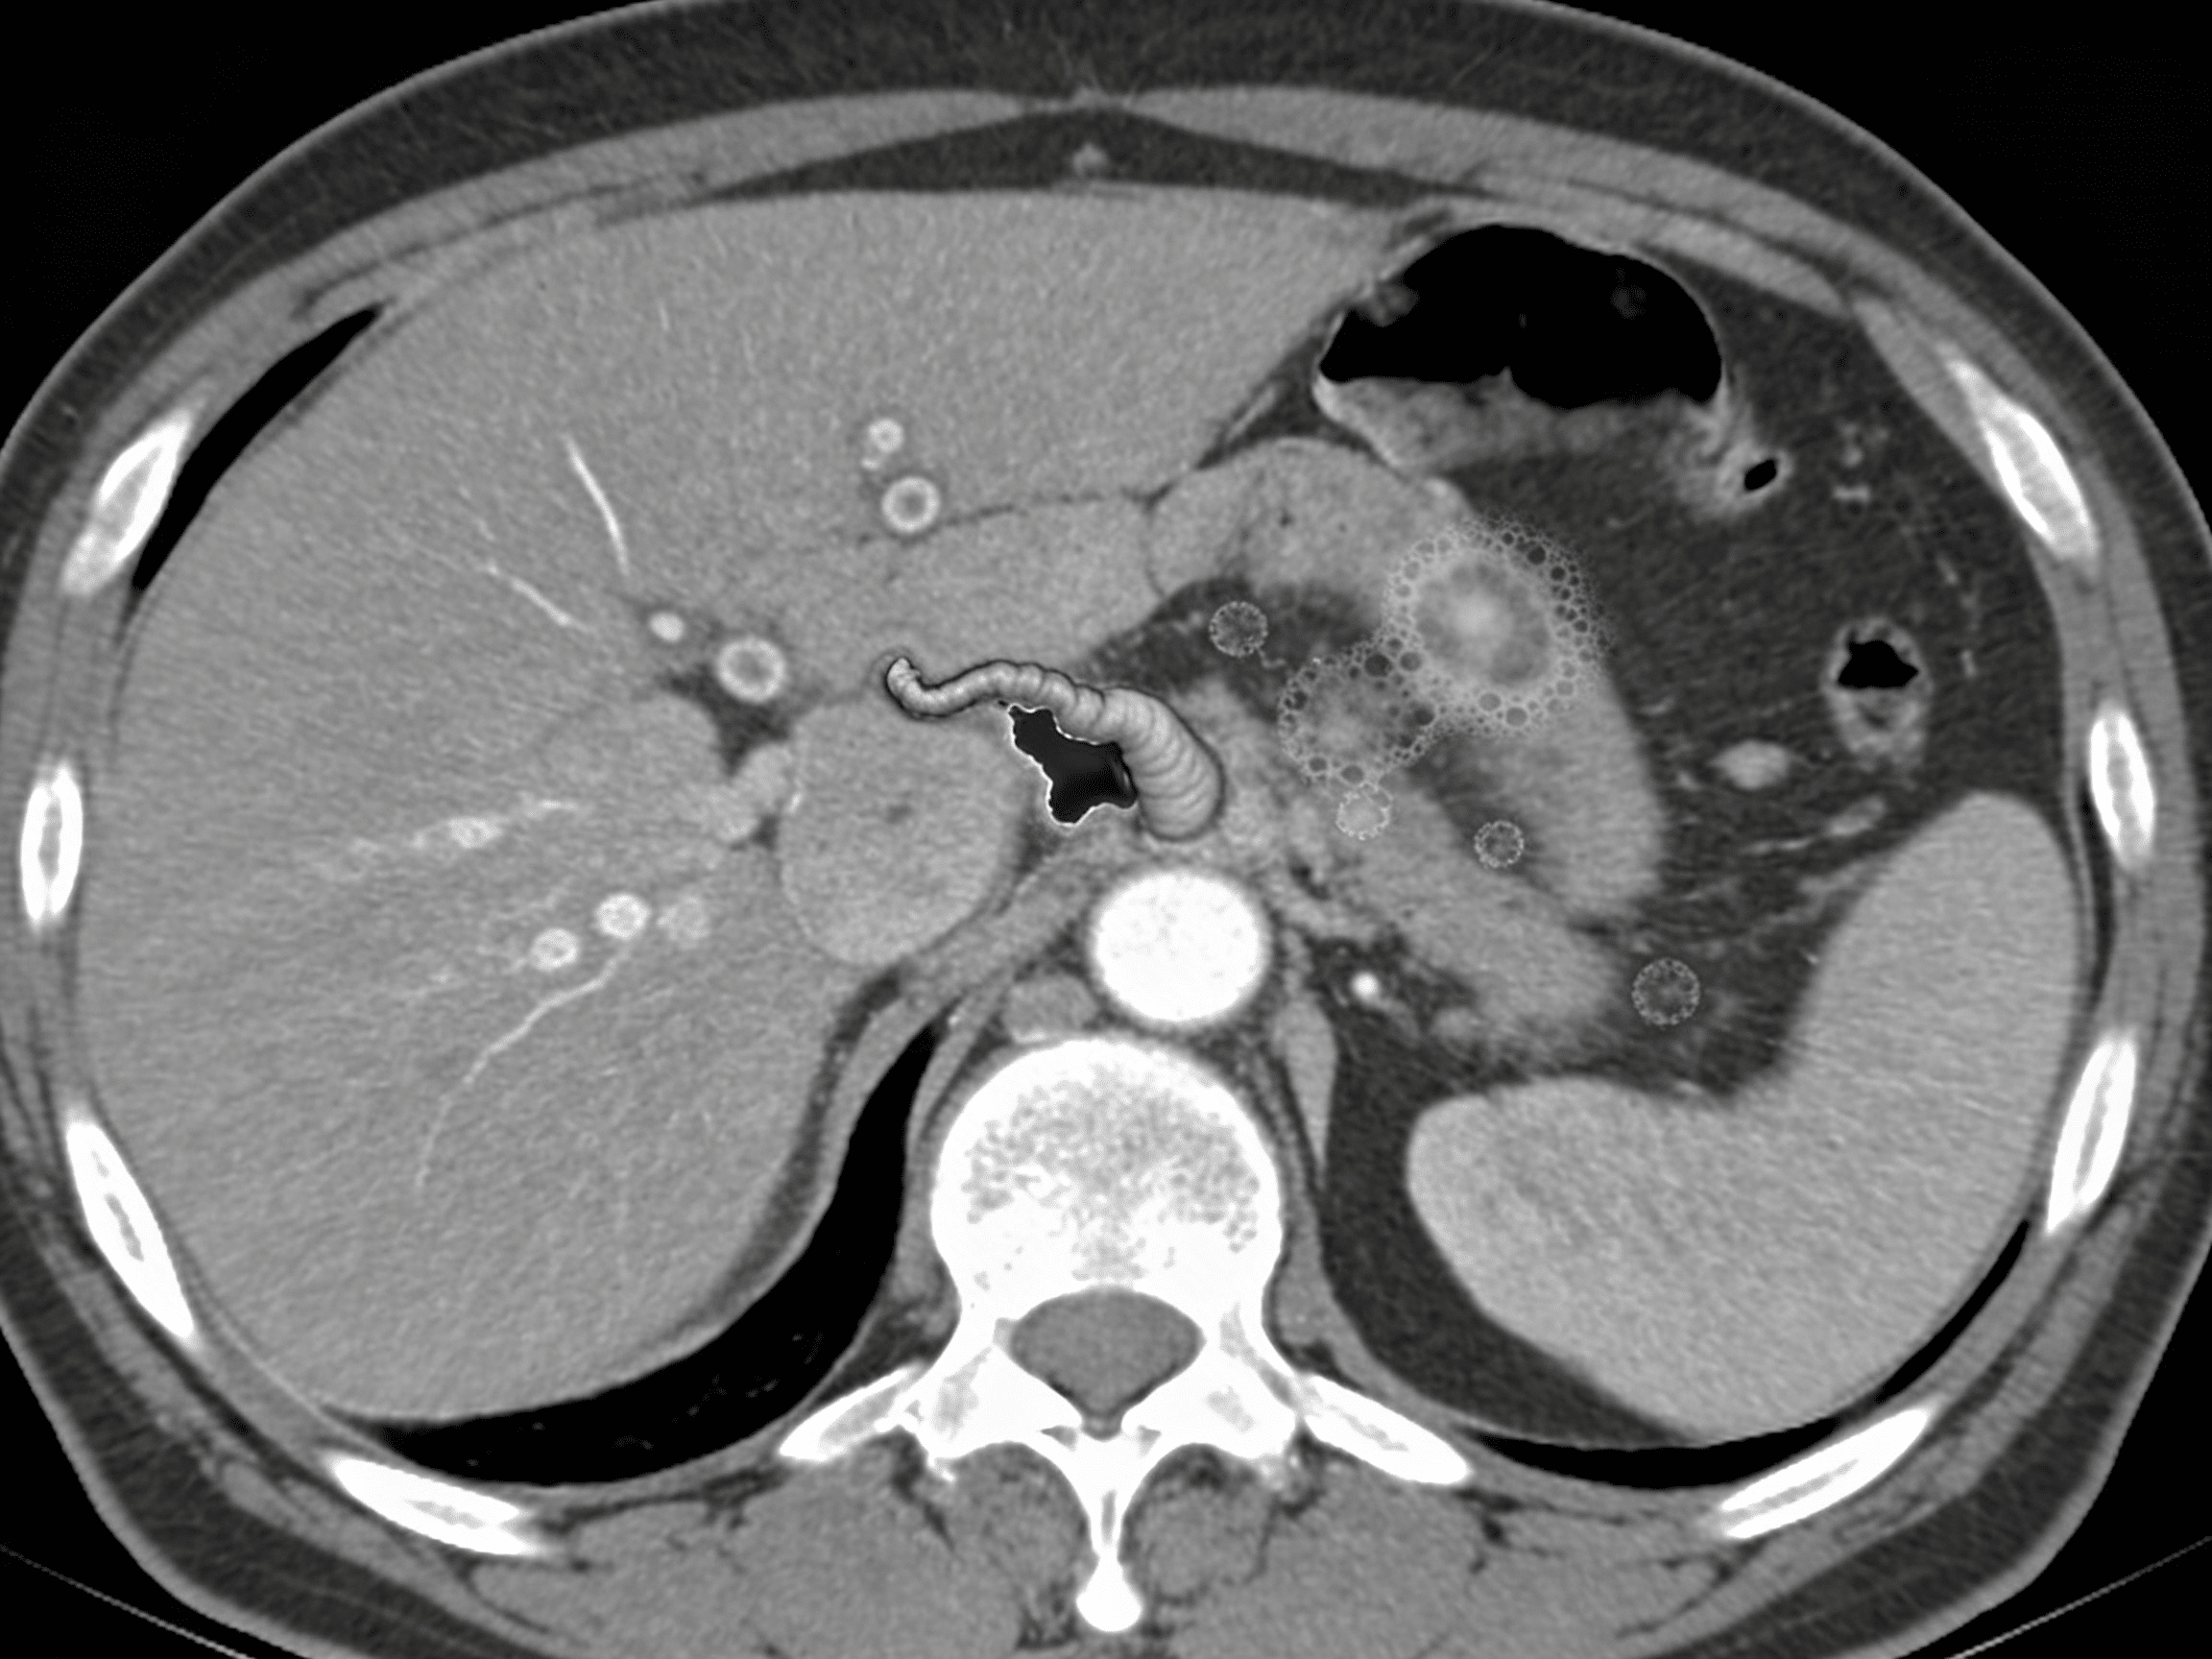

What does appendicitis look like on abdominal CT?

Appendicitis on CT shows appendiceal diameter >6mm, wall thickening >3mm, periappendiceal fat stranding indicating inflammation, and sometimes appendicolith (calcified fecal material) obstructing the lumen. Priority ER emergency physicians identify these findings with 95% sensitivity, immediately differentiating uncomplicated appendicitis requiring straightforward appendectomy from perforated appendicitis showing abscess, free air, or extraluminal fluid requiring different surgical approach with possible drain placement. Negative CT (normal appendix <6mm diameter, no inflammation) effectively excludes appendicitis, avoiding unnecessary surgery while prompting evaluation for alternative diagnoses.

Priority ER's diagnostic capabilities for abdominal CT for suspected appendicitis, perforation, or internal bleeding exceed Joint Commission standards for emergency departments[14], featuring 64-slice multidetector CT scanner providing immediate high-resolution abdominal imaging with arterial, portal venous, and delayed phases identifying appendicitis (sensitivity 95%, specificity 94%), bowel perforation showing extraluminal air or oral contrast, and active arterial bleeding appearing as contrast extravasation requiring angioembolization[15]. Our emergency physicians trained in abdominal CT interpretation identify McBurney's point tenderness correlating with CT findings, periappendiceal fat stranding indicating inflammation, appendicolith suggesting obstruction, and appendiceal diameter >6mm confirming appendicitis requiring surgical consultation within hours preventing perforation.

Advanced imaging through our comprehensive diagnostic capabilities provides CT enterography protocols for small bowel evaluation, rectal contrast administration when pelvic abscess or appendiceal perforation suspected, and immediate interventional radiology consultation when CT identifies active arterial extravasation requiring angiography and coil embolization as alternative to surgery. For trauma patients, our emergency physicians utilize American Association for Surgery of Trauma (AAST) organ injury grading scales determining which solid organ injuries require operative management versus nonoperative observation with serial imaging and hemoglobin monitoring. This comprehensive approach explains why the American College of Radiology appropriateness criteria mandate CT as first-line imaging for suspected appendicitis in adults, replacing ultrasound and clinical diagnosis alone improving diagnostic accuracy from 80% to 98%.